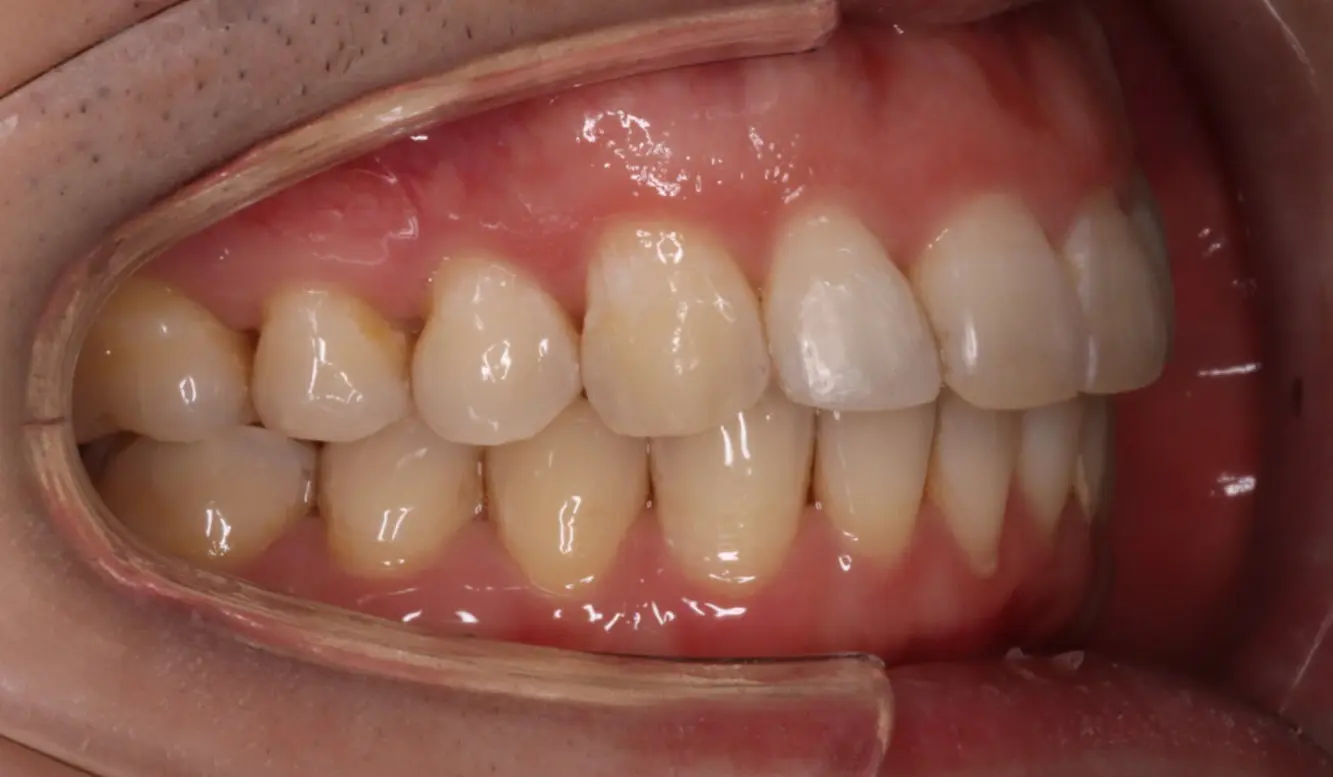

Before

After